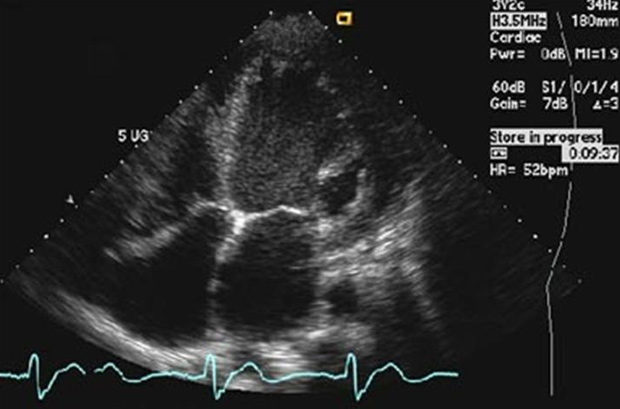

Motor desregulado

Cada coração tem sua cadência, mas alterações bruscas podem levar à morte